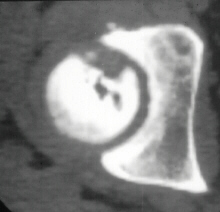

At 28 years of age, he had been having increasing pain in his right hip. He had a limp when he was tired. Positive Trendelenburg's sign was observed on the right. Internal rotation was limited to 25 degrees. All other motions were normal. X-ray showed cystic change. At the 29 years of age, he underwent bone graft of the right femoral head for degenerative cyst. At 35 years of age, only internal rotation was limited to 20 degrees. He still had pain in his hip that relates primarily to weather or to excessive walking. Only internal rotation was limited to 20 degrees. He had hip pain at the extremes of flexion and internal rotation. X-ray showed the progression of the cystic change. CT which was performed because of the question of loose bodies in the hip did not seem likely that the densities were actually in the hip joint. The antero-medial location of the cysts facing the anterior margin of the acetabulum was well depicted in CT.

28 yrs, 29 yrs, 30 yrs, 35 yrs .